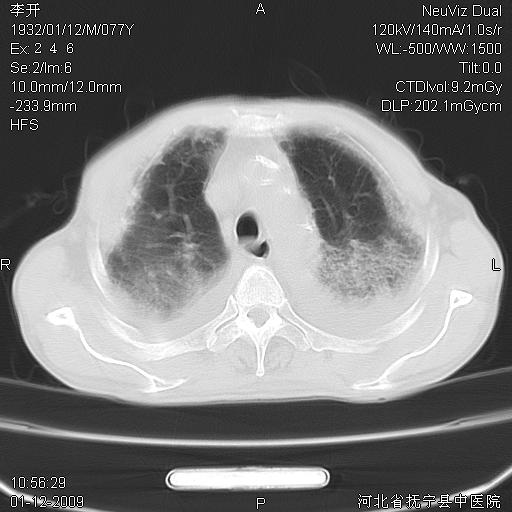

以下是引用黑白光影在2009-1-19 16:49:00的发言:[br]心衰肺水肿;心包、胸腔积液;冠脉钙化;肺部感染。